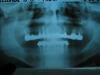

raucher Опубликовано 12 марта, 2009 Автор Поделиться Опубликовано 12 марта, 2009 Фронтальный снимок. За качество прошу извинить, фото с ренген.пленки. Ссылка на комментарий

raucher Опубликовано 12 марта, 2009 Автор Поделиться Опубликовано 12 марта, 2009 Здесь не выйдет одномоментно.В три этапа придется делать: фронтальные импланты, исключая 14 и 23.подсадка кости в боковых сегментах, установка оставшихся имплантов.О непосредственном протезировании я не стал бы говорить даже в переднем сегменте, так как прикус нестабилен.[/qУважаемый Furu объясните последнее предложение: - "О непосредственном протезировании я не стал бы говорить даже в переднем сегменте, так как прикус нестабилен". Ссылка на комментарий